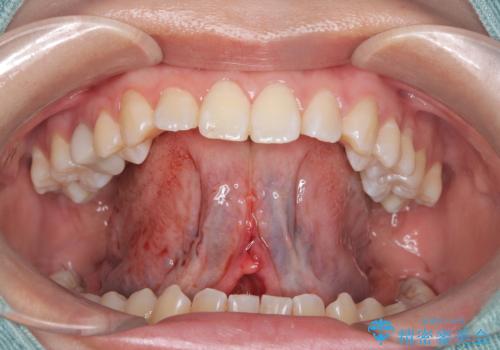

- 「舌が短くて滑舌が悪いので舌小帯を切って欲しい」を主訴に来院された患者様です。

舌小帯切除術を行い舌の可動域を広げ、滑舌の向上を目指しました。

舌小帯切除術は小手術で短い時間で終える事が可能なのでご予約の状況によってはカウンセリング当日に治療を行うことが出来ます。